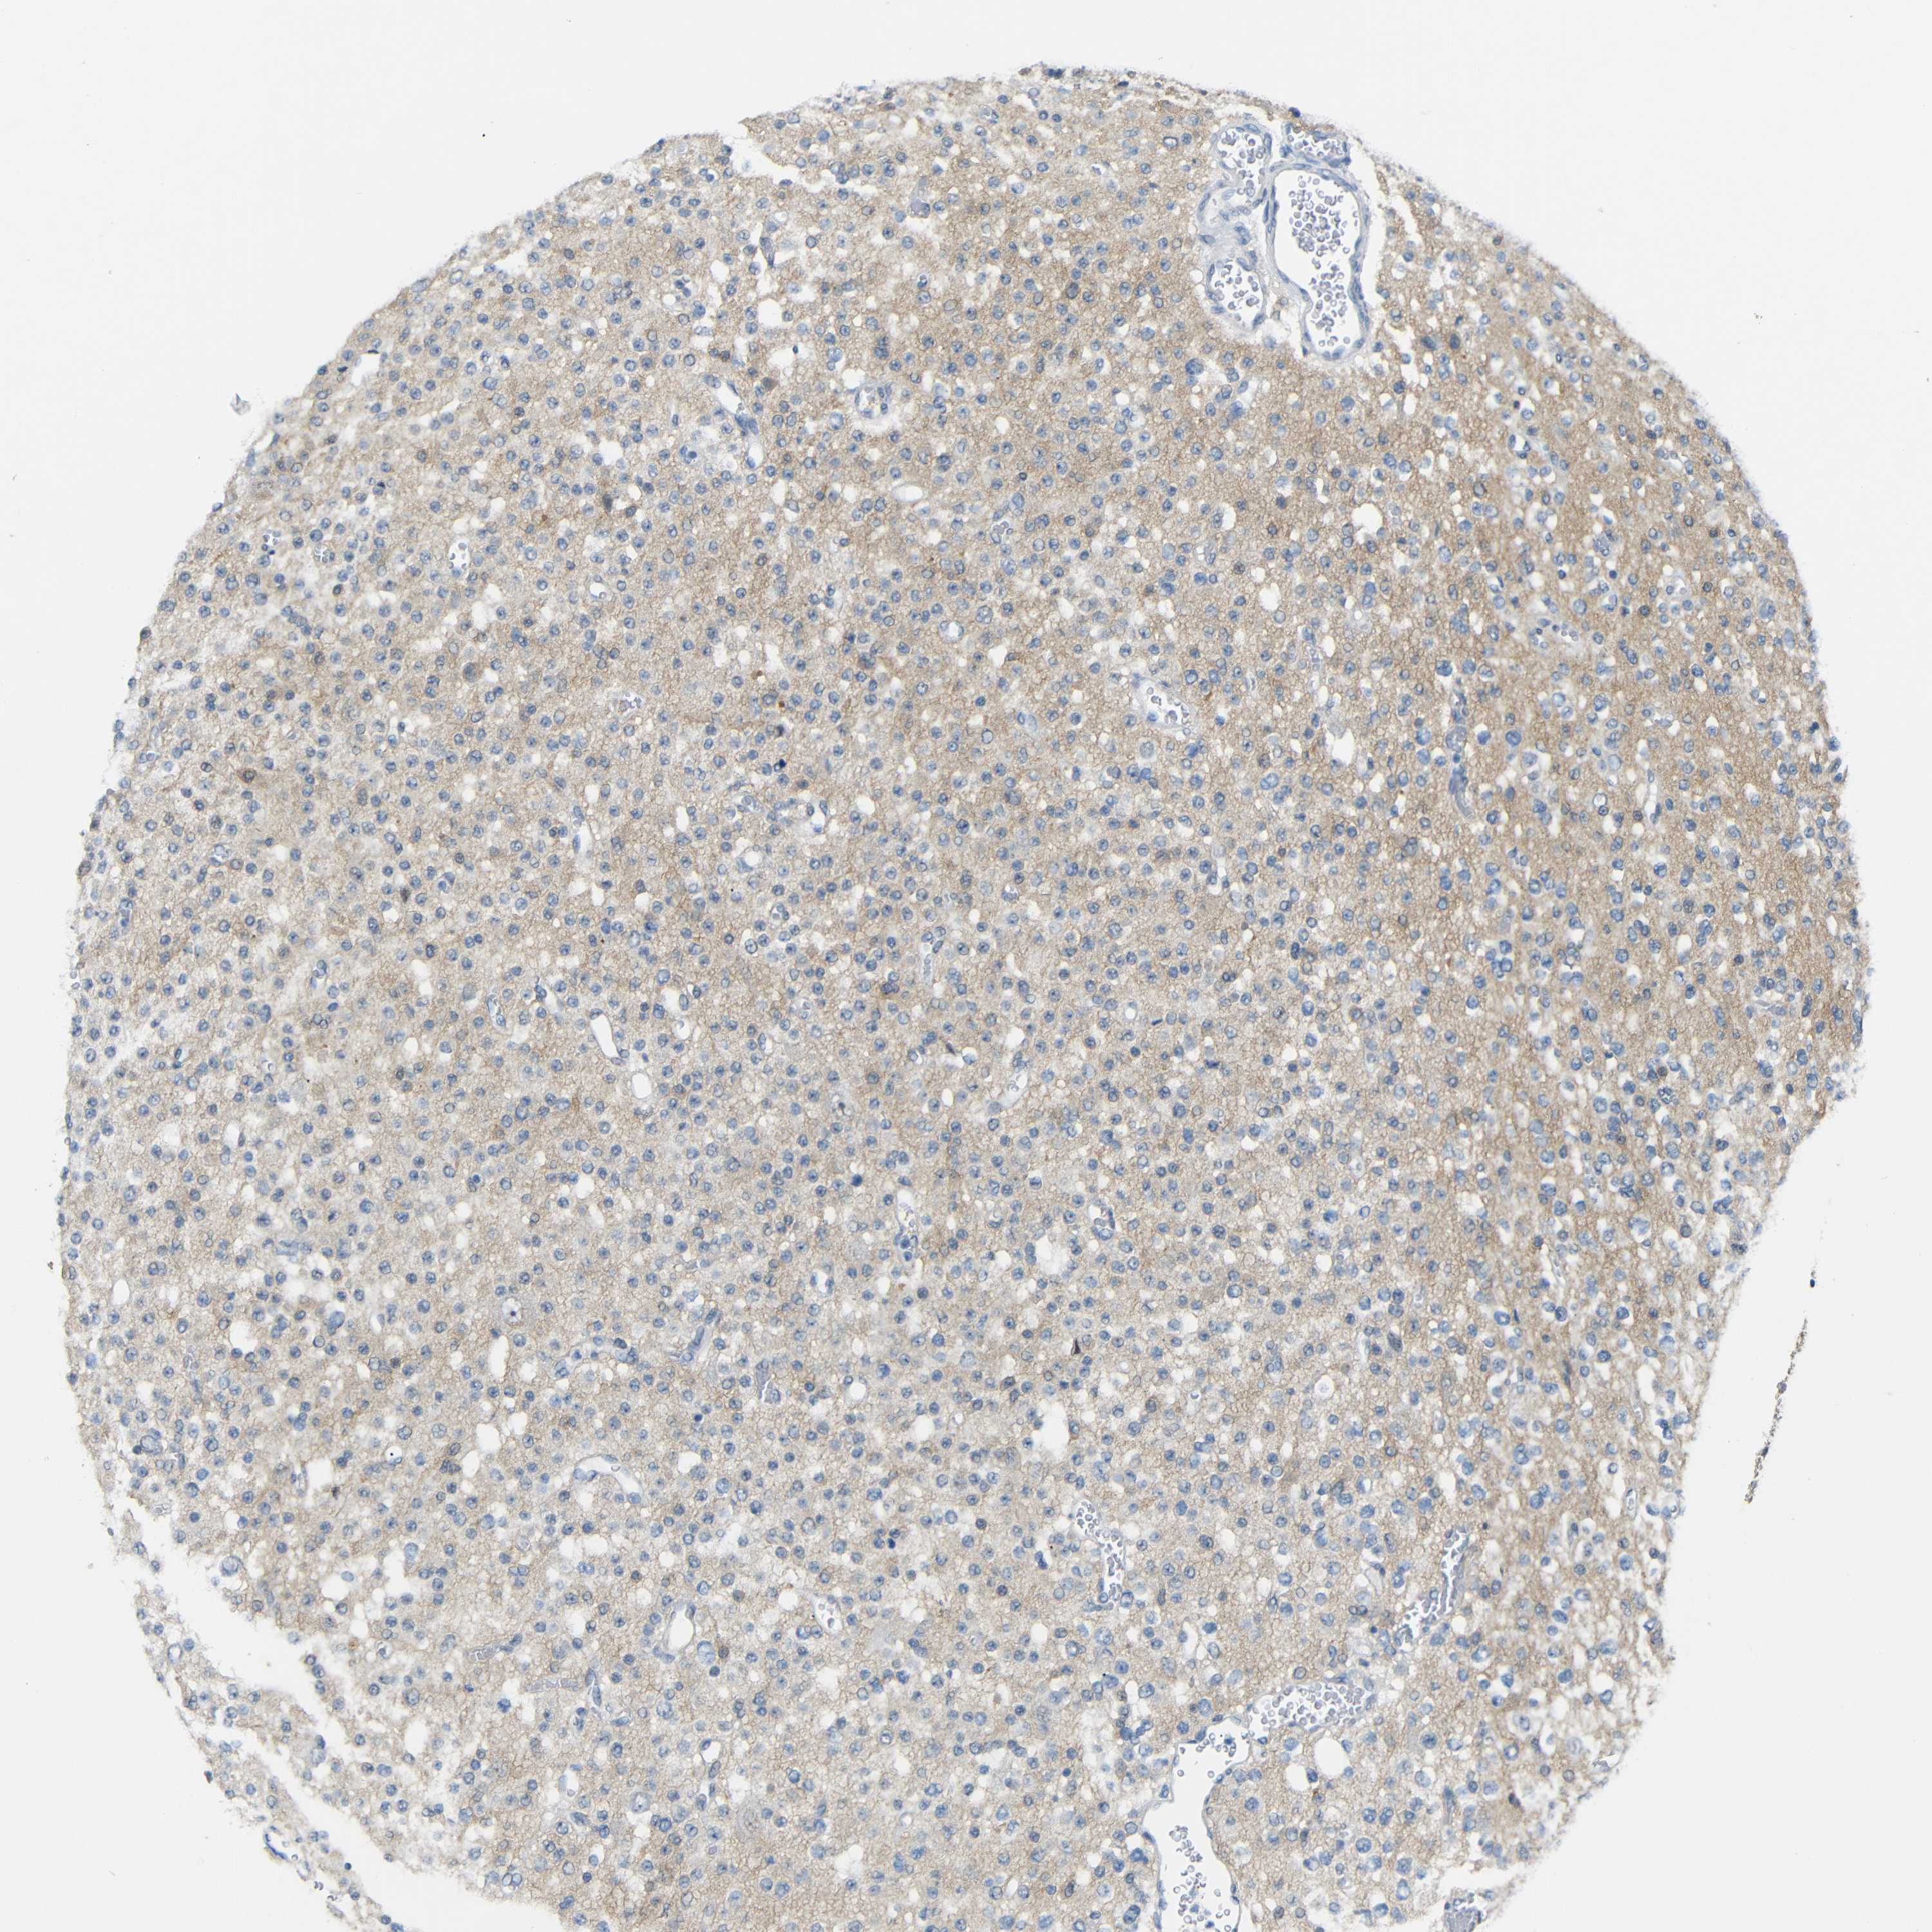

GLIOMA - Protein expressioni

A mouse-over function shows sample information and annotation data. Click on an image to view it in a full screen mode. Samples can be filtered based on level of antibody staining by selecting one or several of the following categories: high, medium, low and not detected. The assay and annotation is described here.

Note that samples used for immunohistochemistry by the Human Protein Atlas do not correspond to samples in the TCGA dataset.

Antibody stainingi

Antibody staining in the annotated cell types in the current human tissue is reported as not detected, low, medium, or high, based on conventional immunohistochemistry profiling in selected tissues. This score is based on the combination of the staining intensity and fraction of stained cells.

Each image is clickable and will lead to virtual microscopy that enables deeper exploration of all samples and also displays staining intensity scores, fraction scores and subcellular localization as well as patient and tissue information for each sample.

Antibody HPA013185

Staining

High

Medium

Low

Not detected

Intensity

Strong

Moderate

Weak

Negative

Quantity

>75%

75%-25%

<25%

None

Location

Nuclear

Cytoplasmic/membranous

Cytoplasmic/membranous,nuclear

Glioma, malignant, High grade

Glioma, malignant, Low grade